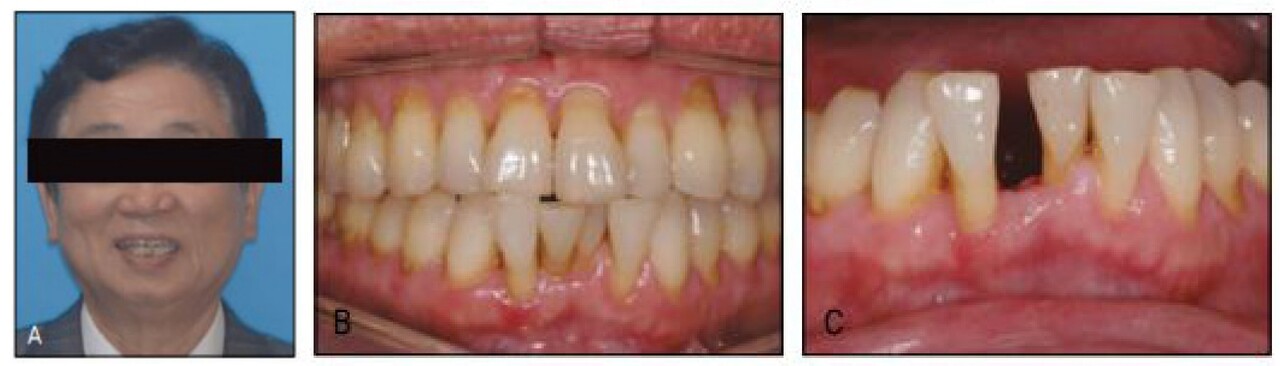

또한 보철을 위한 교정 등 보조적 교정치료의 일환으로 교정치료 필요성이 크게 증가하게 되었다. 예를 들어 하전치 부위 크라우딩 상태에서 어떤 이유로 하나의 절치를 발거하게 되었다면, 발치한 치아주위의 크라우딩을 펴지 않고서는 어떠한 보철도 할 수 없게 된다. 주변 치아의 삭제없이 해당 결손부위 보철을 위해 임플란트가 개발되었는데 환자에게 주위의 크라우딩 치아를 다 발거하고 임플란트 하자 할 수 없고, 브릿지를 한다 하더라도 인접치 위치가 불량한 상태에서 그냥 보철은 대부분 되지 않을 것이며 결국에는 교정치료를 해야 하는 경우가 매우 많다.

진료 편의상 또는 소위 전략적이라는 명분하에 인접치를 발거 하고 보철치료를 권하였을 때 고령환자의 대부분은 이를 거부할 것이며, 지금까지는 나이가 많아서 교정이 안된다고 막연히 생각하였던 그 교정치료를 이제는 당연한 치과치료의 한 과정으로 설명하고 또 실제적으로 시행할 필요성이 증가할 것으로 전망하고 있다(그림 23-2)